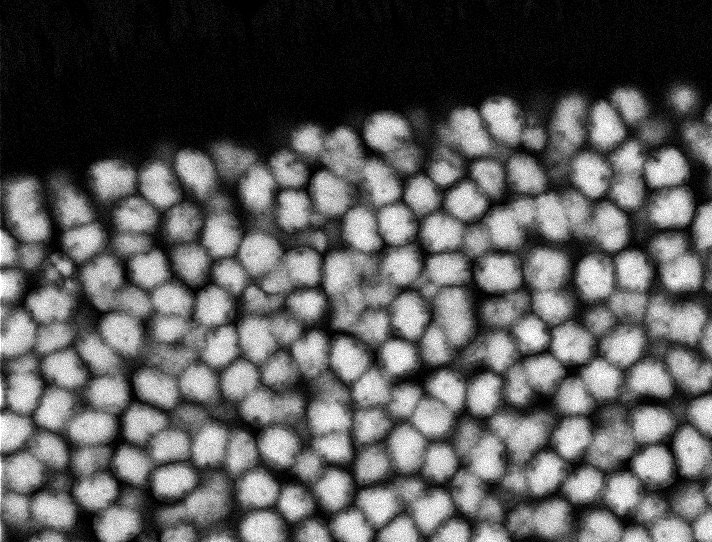

Healthy Retina

Unhealthy Retina